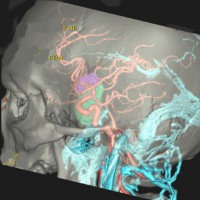

左は下垂体腺腫(緑の腫瘍)が内頚動脈に挟まれていることを示しています。

中央は手術前の下垂体腺腫で,視神経も正常下垂体も位置はわかりません。

右は手術翌日の画像です。黄色の矢印の先が残した正常下垂体組織です。桃色の矢印の先に視神経(視交叉)がはっきり見えています。術後の一時的な尿崩症がありました。クモ膜が残っているので髄液漏は生じませんでした。でも正常下垂体組織(黄色矢印)も視交叉も腫瘍に圧迫されてペラペラになっていますから,いつもうまく行くとは限りません。